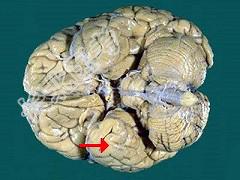

- 单项选择题如图箭头所示为大脑哪个部位 ( )

A、额叶

B、颞叶

C、枕叶

D、顶叶

E、岛叶